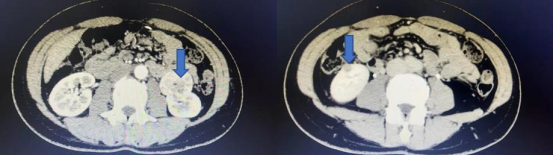

今年48岁的齐女士因体检发现左肾长了一个4公分大小的肿瘤,住院后为进一步明确诊断,完善肾脏增强CT,结果意外发现右肾也存在一个大小约1公分的肿瘤,王女士得知后决定完善全身PET-CT检查,PET-CT提示双肾病变,未见转移。王春阳告诉患者家属目前患者双肾肿瘤还没有转移,尽快手术是最好的治疗方案。为完整切除双侧肾肿瘤,并且最大限度保留肾脏功能,同时实现微创效果,在患者及家属积极要求下,王春阳团队决定为患者行机器人辅助腹腔镜下双肾肿瘤切除术。

王春阳介绍,双肾肿瘤一期同时切除手术难度较大,但同时机器人辅助腹腔镜手术系统对于双肾肿瘤一期切除有其独有的优势——切口仅仅增加一个即可完成双肾肿瘤的完整切除,并且可以最大限度地实现“零缺血”,即术中可不阻断肾动脉而完整切除肿瘤,最大限度的保留了肾脏功能,为患者之后的生活质量提供了保证。